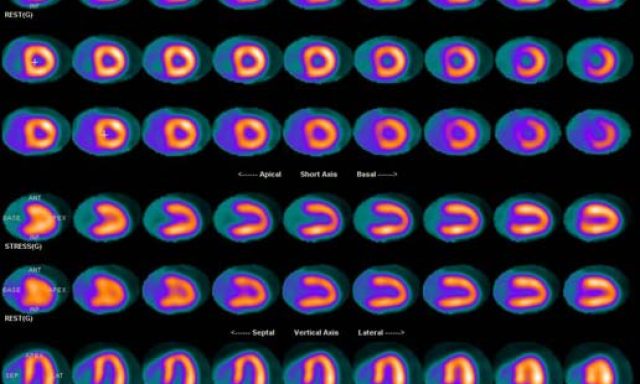

Are you looking for the nuclear medicine service and imaging equipment? Simplified Imaging Solution provides a complete turnkey solution to…